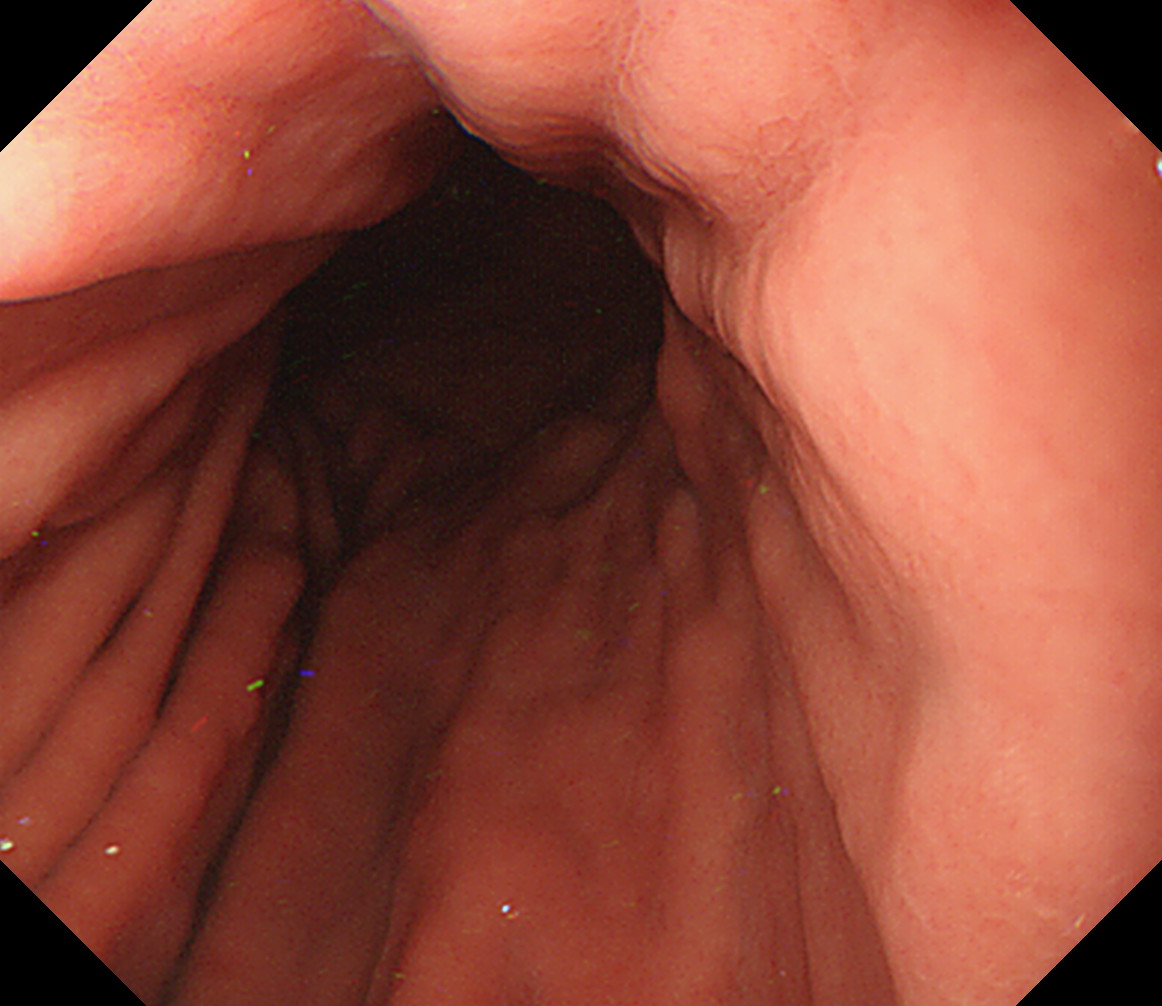

11 胃角部後壁 [見下ろし]になります 中部食道

12 胃角部小弯 [J反転]見上げになります 胃角部後壁

13 胃角部前壁 再度、[見下ろし]になります 胃角部前壁

14 体下部小弯(角上部) [J反転]して以降見上げです 体下部小弯(角上部)

15 体中部小弯 接線になり見逃しやすい部位です 体中部小弯

16 体上部小弯 接線になり見逃しやすい部位です 体上部小弯